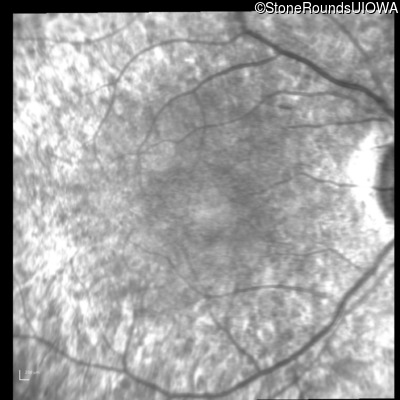

Visit at age: 21 years

Infrared Fundus Photograph - Right - 20/25 -2

Exemplar

Infrared Fundus Photograph - Left - 20/32